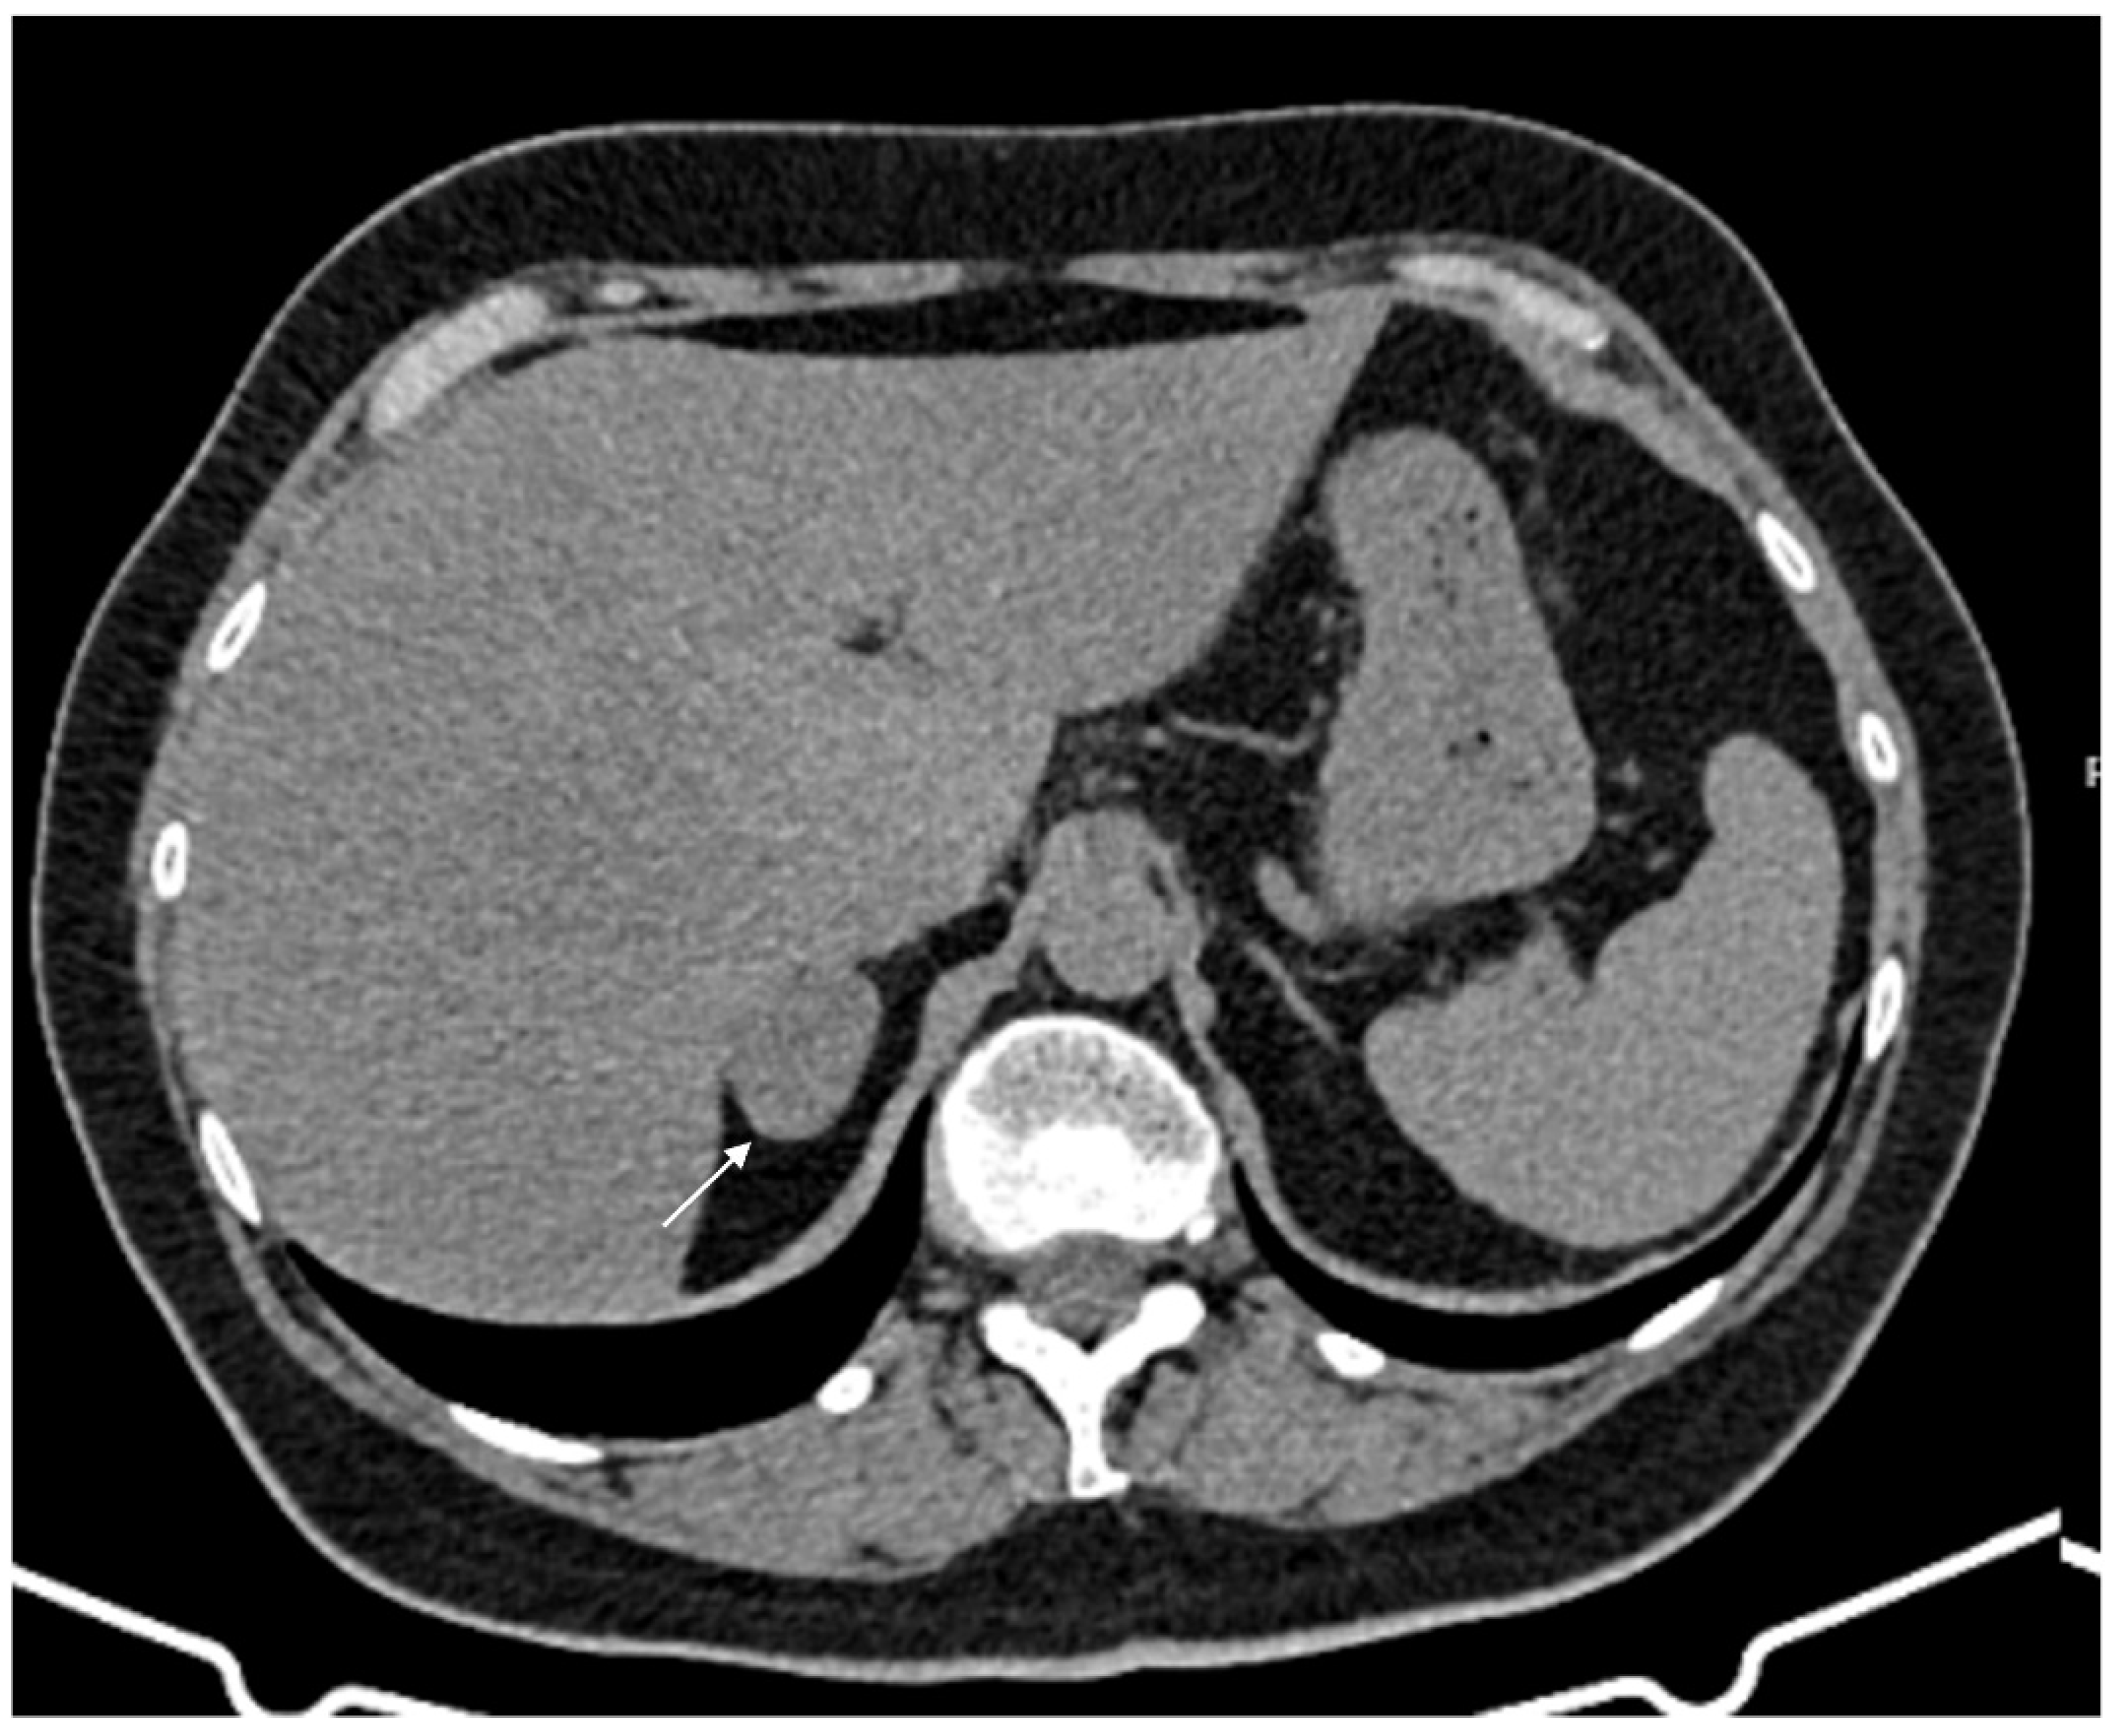

Figure 5.

Doubtful hypodense nodule (arrow) inside the left adrenal gland on basal CT (A); in coronal reconstructions the adrenal gland has normal morphology (B).